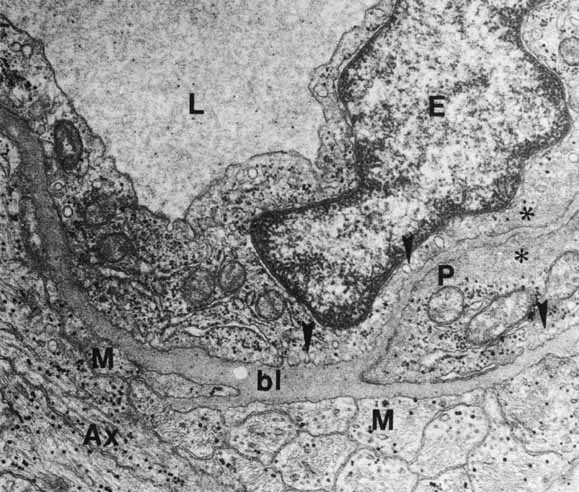

The photoreceptor outer segments have two important connections. One of these is to the inner segment, which is actually the cell body of the photoreceptor (see Fig. 21). The other connection is to the extracellular matrix that separates the photoreceptor outer segment from the pigment epithelial cell. Radioactive tracer experiments suggest that the sources of this extracellular matrix substance are the pigment epithelial and photoreceptor cells.99,100 The material, a glycoprotein consisting of chondroitin sulfate and sialic acid, is secreted into the space between the outer segments and the pigment epithelial cells by vesicles that originate in both cells. The function of this mucopolysaccharide-rich matrix is not well understood. It may provide a major route by which metabolites and nutrients pass between photoreceptor cells and their vascular supply. It may constitute the only intercellular bond between the outer segments of photoreceptors and the pigment epithelial cells, because there are no cellular connections such as tight junctions between these cells (see Fig. 23). Recent studies have identified interphotoreceptor retinol-binding protein as a major component of this matrix.100 This glycoprotein is believed to mediate the transport of a vitamin A derivative, retinol, between the photoreceptor and the pigment epithelium.

The connection of the outer to the inner segment of the photoreceptor is through a slender (0.2–0.3 μm in diameter) neck that is eccentric toward one side of the cell (see Fig. 21). The cilium, which is the embryonic basis for origin of the photoreceptors, is located in the neck and extends into the basal one third of the outer segment. It has nine pairs of microtubules. However, unlike motile cilia, the cilium has no microtubules centrally. The microtubules end in a modified centriole in the apex of the inner segment. The cilium functions as a conduit for metabolic materials going from the inner to the outer segments.

Inner Segments

The inner segment of the photoreceptor is the portion of the cell that metabolically services the outer segment. Whereas the outer segment shows high differentiation, containing only equipment necessary for the photoreceptor process, the inner segment possesses the cellular machinery essential for the metabolic and synthetic functions of the cell. There are two distinct morphologic regions in the inner segment, the ellipsoid and the myoid. The most prominent feature of the outer portion, or ellipsoid, of the inner segment is the abundance of large mitochondria at the apex (see Fig. 21). The ellipsoid appears to be more sensitive to anoxia than any other part of the photoreceptor cell.101 The staining characteristics of this area vary with the state of metabolic activity of the photoreceptor cell and may account for the subtle staining differences seen in the various types of photoreceptor cells. The mitochondria in the ellipsoid are compactly arranged. They are present in higher concentration in retinas with poor vasculature. In addition, the cones have a higher concentration and greater absolute number of mitochondria than the rods. There may be up to 600 mitochondria per cone.87 These mitochondria contain the normal enzymes for oxidative production of energy.102

The cilium or basal body arises from one of a pair of centrioles at right angles to one another in the distal portion of the ellipsoid. From the basal body originates the cross-striated fibril system of rootlets that course through the inner segment (see Fig. 21). The ciliary rootlets are composed of bundles of several hundred fibrils with a periodic alternation of light and dark zones 45 nm wide. They may extend as far as the nucleus of the cell. Their function remains speculative, although histochemical evidence suggests that they may play a role in energy or even in signal conduction. The energy-related enzyme, ATPase, has been found in the fibrils of these rootlets.103

The major protein synthetic activity and assembling of synthetic products in the inner segment take place at its proximal portion, or “myoid,” which houses the rough endoplasmic reticulum, ribosomes, and large Golgi complex associated with numerous vesicles. Because this region may be the source of the acid mucopolysaccharide in the extracellular space between the photoreceptor outer segments, disturbances of this synthetic or assembling facility could result in weakening of the normal retina-pigment epithelium adhesion. Such a defect could make this union more delicate and subject to separation in the presence of a retinal tear or exudative process originating from either the retina or the choroid.

Outer Nuclear Layer